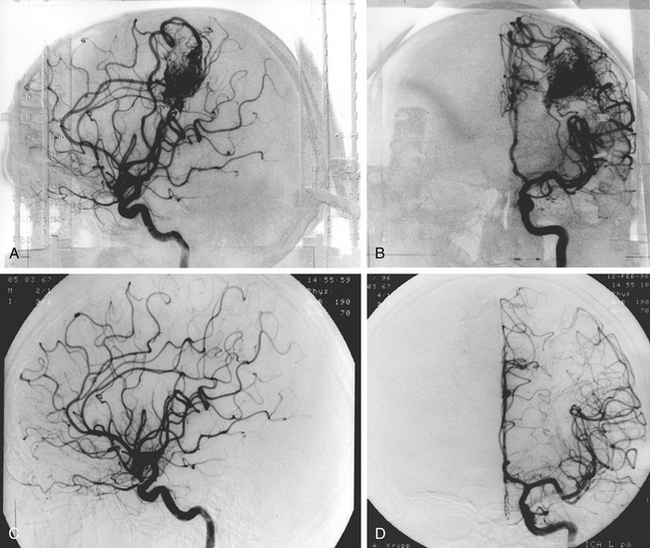

Хирургические процессы при эмболизации гемангиомы на фото

Раздел: Снимки-откровения